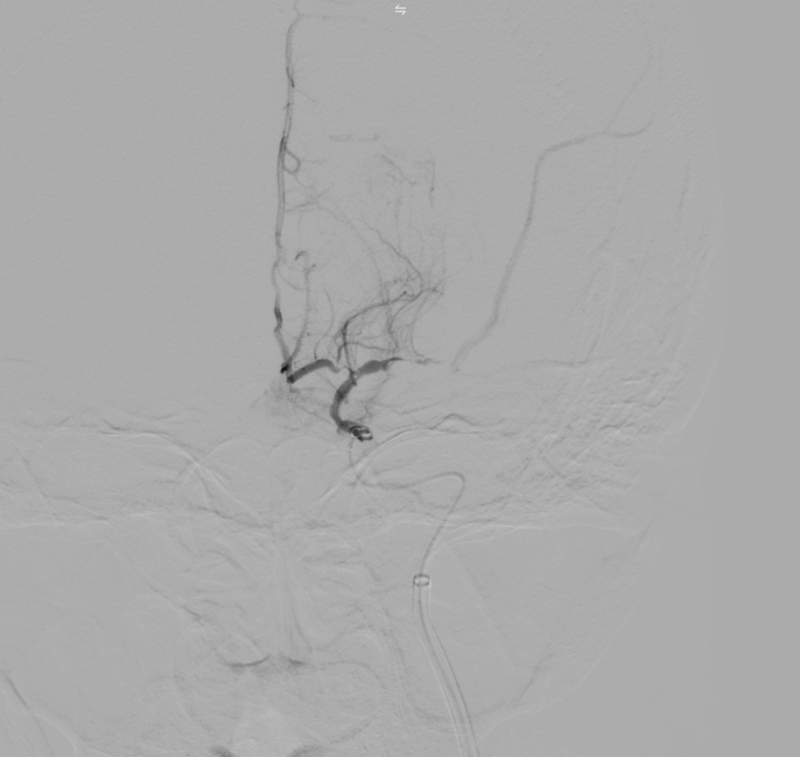

Kết quả chụp DSA xác định tắc động mạch não giữa trái đoạn M1 do hẹp nặng. Kíp can thiệp đã tiến hành nong bóng tái thông mạch máu, khôi phục dòng chảy lên não thành công.

Hình ảnh: DSA trong can thiệp hẹp nặng M1

Hình ảnh: Chụp DSA trước can thiệp thấy tắc M1 trái